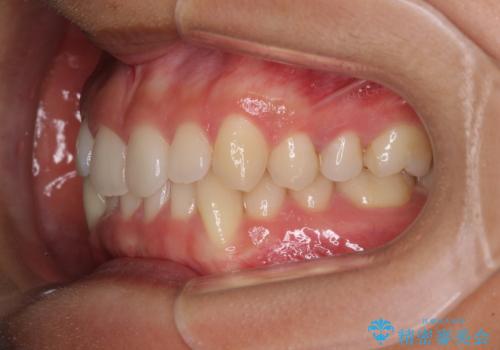

- 下顎の八重歯を気にして来院された患者様です。

マウスピース矯正でもワイヤー矯正でも対応可能であり、マウスピースによる治療を希望されたため、インビザラインを用いることとしました。

下顎前歯にデコボコが集中していたため、顎間ゴムによる後方移動とIPR(歯と歯の間を削ること)により歯列を整えることとしました。

しっかりとマウスピースを装着してくださったおかげで、スムーズに治療を終えることができました。

矯正治療途中で右下奥歯の虫歯治療を近医で行ったようで、既に神経が失活していたと合わせて矯正治療後に補綴治療を行う予定です。